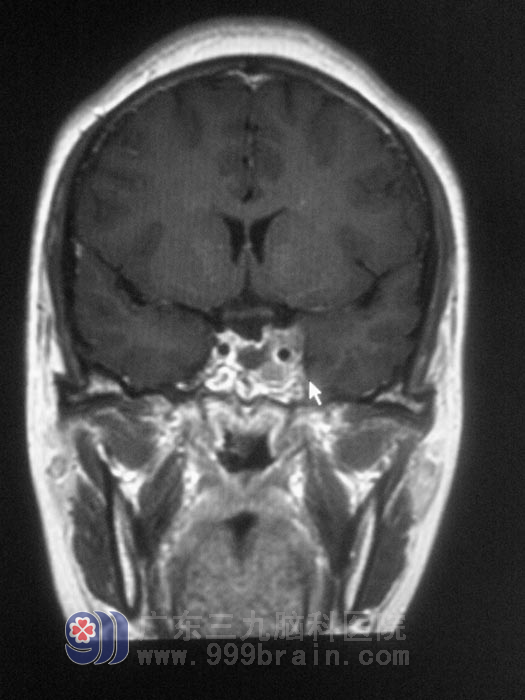

经人介绍,李小姐来到广东三九脑科医院垂体瘤诊疗中心,术前泌乳素171微摩尔每升,MR提示肿瘤大小为2.0*2.0*3.0cm,经讨论决定行经鼻蝶入路微创手术。11月22日,经德国进口导航仪定位,由垂体瘤诊疗中心鲁明主任主刀,在显微镜下见肿瘤呈淡红色胶状,予肿瘤切除,术后未出现脑脊液漏、视力视野损害及尿崩等并发症,复查泌乳素下降为37.6微摩尔每升。病理结果为:多激素分泌型垂体腺瘤。李小姐这颗悬着的心总算放下来了,恢复了以前的快乐生活。李小姐说广东三九脑科医院为她找到了起病原因,并治好了她,以后她自己也会注意,定期复查,保持良好心态。http://www.999brain.com/

术后